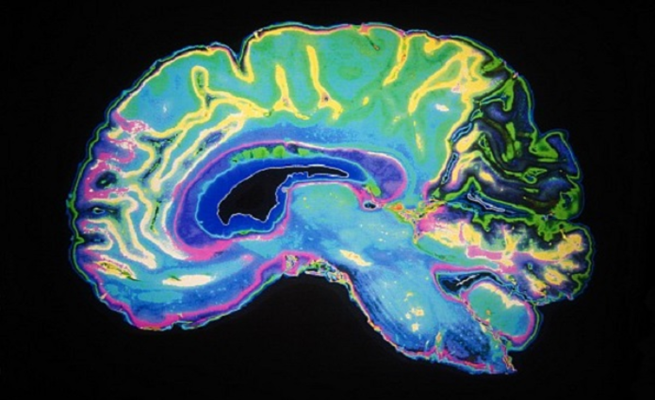

اكتشف العلماء لأول مرة، سر كيفية تخلص #الدماغ من المخلفات أو المواد السامة، وذلك لوجود أنابيب صرف خاصة به قادرة على القيام بهذه المهمة.

ولأول مرة، وجد الباحثون الأوعية التي تنقل المواد الضارة أو الخلايا الميتة خارج الدماغ للحفاظ على صحته، ويمكن أن تساعد هذه النتائج العلماء على فهم الأمراض العصبية مثل مرض الزهايمر الذي يعتقد بأنه ناجم عن تراكم لويحات لزجة يفشل الدماغ في إزالتها.

واستخدم الدكتور رايش وفريقه تقنية التصوير بالرنين المغناطيسي لمسح أدمغة خمسة متطوعين أصحاء بعد حقنهم بصبغة مغناطيسية مصممة لإظهار الأوعية، وهو ما مكنه من الوصول إلى هذه النتائج المفاجئة بوجود نظام لمفاوي في الدماغ، ويمكن لهذه النتائج أن “تغير بشكل جوهري طريقة تفكيرنا في كيفية ربط الدماغ بالجهاز المناعي”.